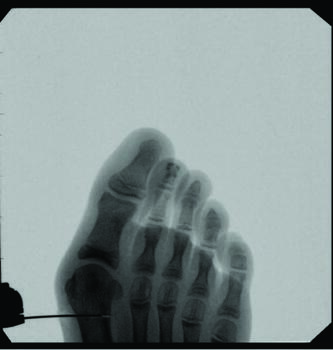

Minimally Invasive Approaches To Juvenile Hallux Abducto Valgus Deformity

One can allow early mobilization by immediate weight-bearing in the postoperative course, most notably providing a decrease in adhesions and consequent stiffness of the joint. Another advantage includes multiple viable fixation options, including splintage with a Steinmann pin through external fixation. Many long-term risks of internal fixation include foreign body reaction, growth disturbance, chronic infection, corrosion, implant migration, and potential interference in orthopedic treatment later in life.14 Schmittenbecher and coworkers described risks of implant removal in children with various fixation options, concluding that each patient’s treatment selection must weigh the benefits and risks.14 Steinmann pin fixation may, in my experience, alleviate these risks, removing it around four weeks postoperatively.

As we all know, in stage two of fracture healing, the bone will form a fibrocartilaginous callus; this internal callus houses new blood vessels in the newly formed spongy trabeculae. Therefore, at four-week postoperative radiographs, one may not appreciate a bone bridge across the osteotomy site. As long as an intracapsular osteotomy took place through a minimal approach, I find the capital fragment should stay inherently stable. In my experience, the osteotomy site will form a robust bone bridge through mechanotransduction.

Some surgeons hypothesize that the lack of lateral capsular or tendon balancing procedures allows an increase in soft tissue tension to provide stability to the capital fragment of a construct that is not inherently stable. Common complications include relapse or malalignment, where the capital fragment achieves excess dorsiflexion or plantarflexion. The most common complication reported by some is pin site infection at 19.4 percent, successfully treated with oral antibiotics.10